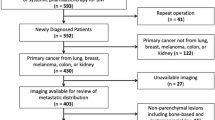

Prospectively and consecutively collected epidemiologic, imaging and histopathological data of every patient having undergone brain tumor surgery at our tertiary care hospital over a 4-year period (April 2009 to March 2013) was reviewed. The following were criteria for the inclusion of patients in the study: (i) a histopathologically confirmed NT, PCNSL or metastases after biopsy or resection, (ii) an intraparenchymal encephalic tumor location (supra-, infratentorial or both), (iii) first diagnosis without any pretreatment, and (iv) availability of complete standardized preoperative high resolution magnetic resonance imaging (MRI) data (technical details in Supplementary methods). Patients with (i) recurrent or pretreated brain tumors, (ii) extraaxial or spinal tumor location, (iii) inconclusive histopathological results, (iv) MRI data not fulfilling the mentioned requirements, or (v) any history of previous cranial surgery were excluded.

Of 690 patients with intraparenchymal neoplasms 42 (6%) were excluded due to inconclusive histopathological results (n = 21, 3.0%), incomplete MRI data (n = 19, 2.8%) or previous cranial surgery (n = 2, 0.3%) (Supplementary Table S1). Of the 648 patients included, 419 (65%) were diagnosed with a NT, 28 (5%) with a PCNSL and 201 (31%) with metastases. Epidemiologic cohort data and details on histopathological results are provided in Supplementary Tables S1 and S2, respectively.